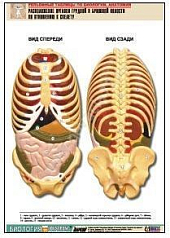

Комплект включает в себя 21 таблицу следующего содержания:

20. Расположение органов грудной и брюшной полостей по отношению к скелету;